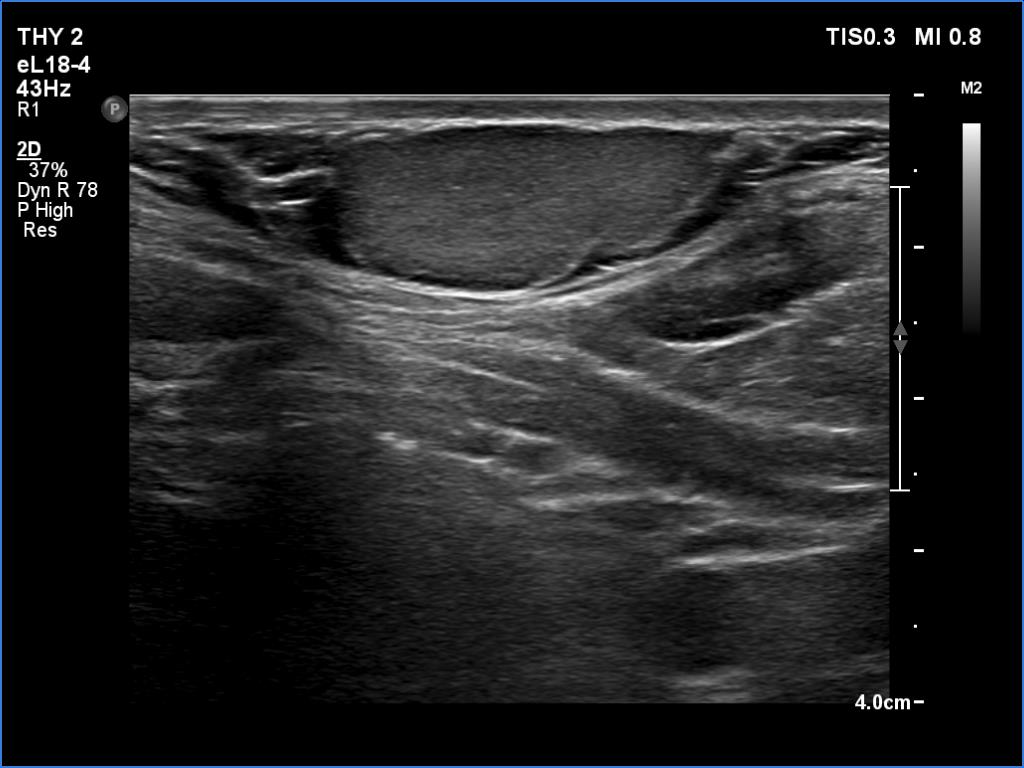

Ultrasonography. The thyroid was echonormal and had several small cystic lesions without any clinical or oncological importance. According to the palpable mass, a moderately hypoechoic lesion was detected several centimeters under the thyroid in the middle of the neck. The lesion was within the muscle tissue. It was homogeneous and presented no vascularity.